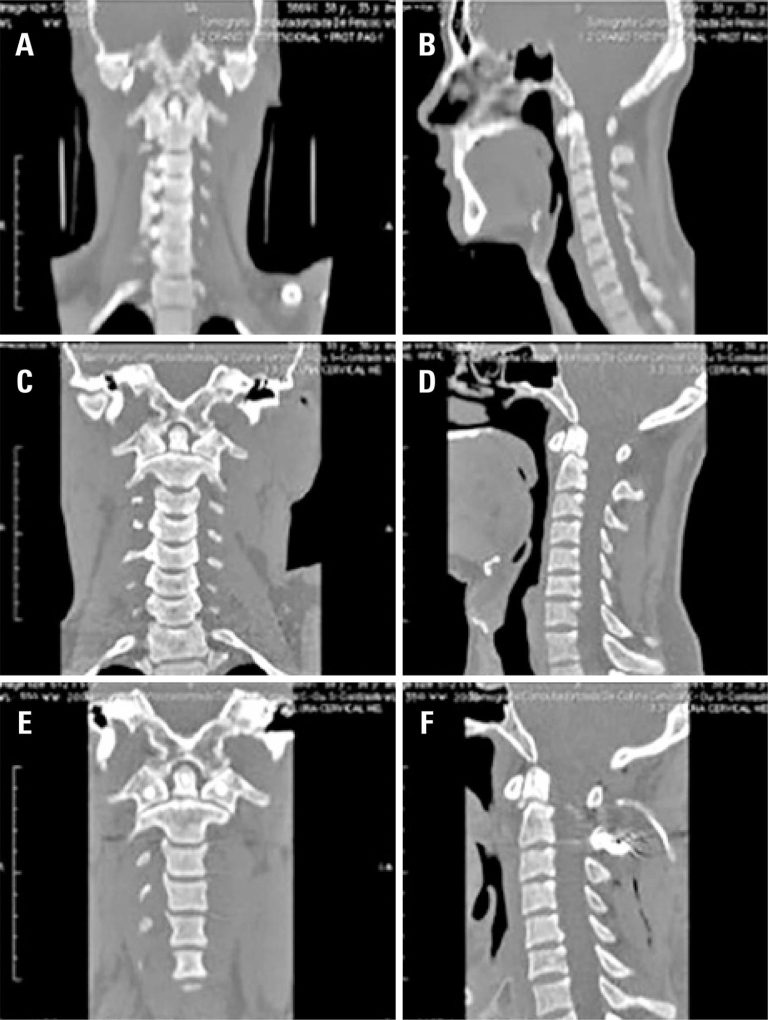

Retrospective analysis of a case series of patients with traumatic injuries to the craniocervical junction

We analyzed 37 patients, 73% were men with mean age of 41.7 years. Of these, 32% were submitted to initial surgical treatment and 68% received conservative treatment. Seven (29%) underwent surgery subsequently. In the surgical group, there were seven cases of odontoid type II fractures, two cases of fracture of posterior elements of the axis, one case of C1-C2 dislocation with associated fractured C2, one case of occipitocervical dislocation, and one case of combined C1 and C2 fractures, and facet dislocation. Only one patient had neurological déficit that improved after treatment. Two surgical complications were seen: a liquoric fistula and one surgical wound infection (reaproached). In the group treated conservatively, odontoid fractures (eight cases) and fractures of the posterior elements of C2 (five cases) were more frequent. In two cases, in addition to the injuries of the craniocervical junction, there were fractures in other segments of the spine. None of the patients who underwent conservative treatment presented neurological deterioration.

Although injuries of craniocervical junction are relatively rare, they usually involve fractures of the odontoid and the posterior elements of the axis. Our results recommend early surgical treatment for type II odontoid fractures and ligament injuries, the conservative treatment for other injuries.